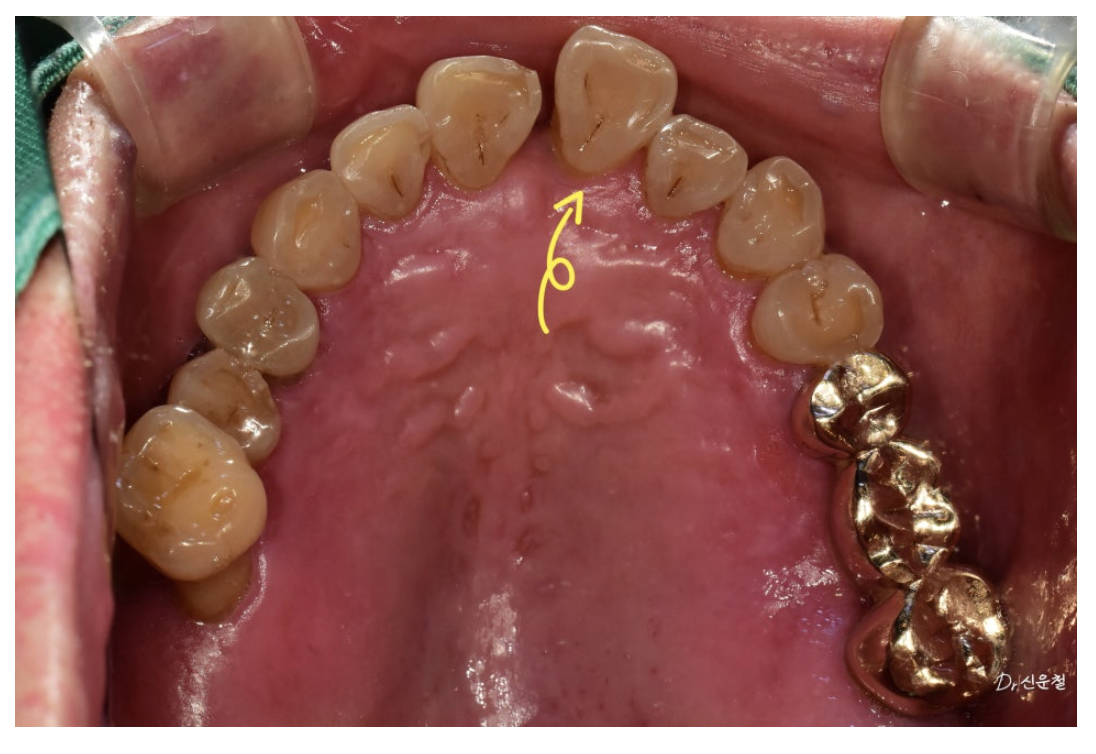

② 앞니가 제자리에서 벗어난 ‘전위 치아’

위 앞니는

잇몸 약화

치아 사이 공간 증가

한쪽 방향으로 반복된 씹는 습관

때문에 앞쪽으로 밀려 나온 상태(전위)였습니다.

4단계: 앞니는 최대한 유지 → 브릿지로 위치 회복

앞니는 가능하면 빼지 않는 것이 원칙입니다.

옆 치아와 연결해 브릿지로 위치를 제자리로 복원했습니다.